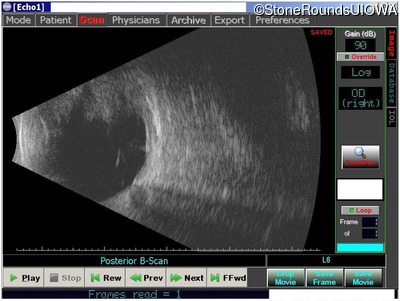

B-Scan Ultrasonography - Left - unknown

Exemplar